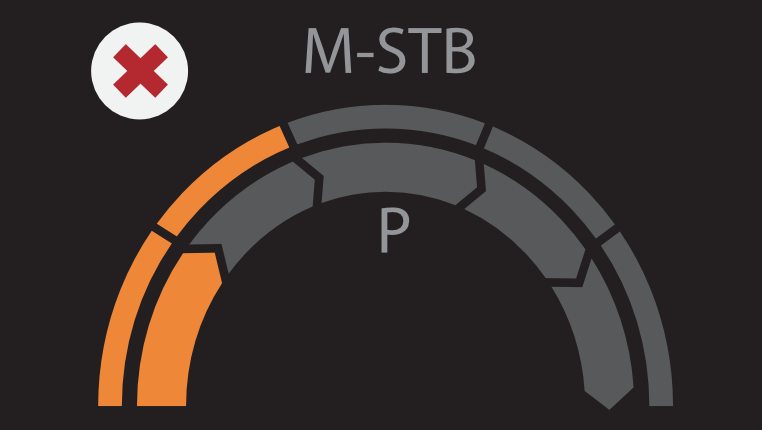

VÃĄrias solu??es de ultrassom*

â Sonda de ultrassom profissional para facilitar o exame de ascite, etc.

â Pun??o guiada por ultrassom dedicado para aprimorar a precis?o das biÃģpsias

â A excelente qualidade de imagem e as fun??es de ultrassom permitem uma avalia??o abrangente da morfologia e hemodin?mica do fÃgado.

â Pun??o guiada por ultrassom dedicado para aprimorar a precis?o das biÃģpsias

â A excelente qualidade de imagem e as fun??es de ultrassom permitem uma avalia??o abrangente da morfologia e hemodin?mica do fÃgado.

* DisponÃvel no Hepatus 6